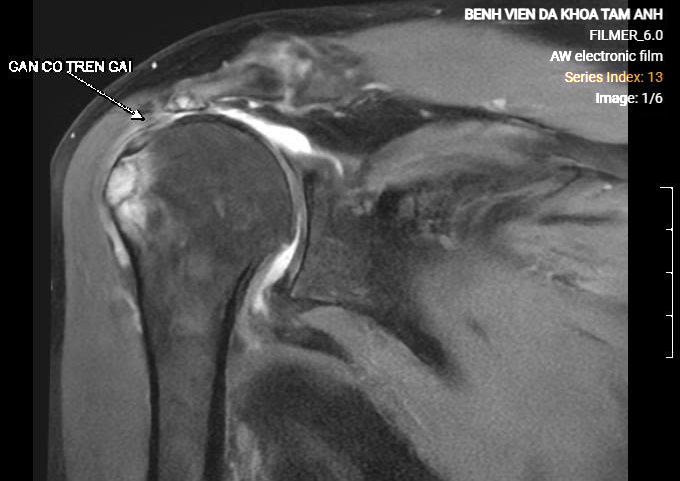

Phim chụp MRI của bà Vân cho thấy gân trên gai đứt hoàn toàn, co rút. Ảnh: Bệnh viện Đa khoa Tâm Anh

BS.CKII Nguyễn Ngọc Tiệp, khoa Chấn thương Chỉnh hình, Bệnh viện Đa khoa Tâm Anh Hà Nội, cho biết kết quả chụp MRI khớp vai bà Vân ghi nhận gân cơ dưới gai đứt bán phần, gân cơ trên gai đứt hoàn toàn, teo mỡ, đầu gân co rút sâu vào trong 4 cm so với điểm bám. Các gân cơ chóp xoay khác viêm, phù nề.